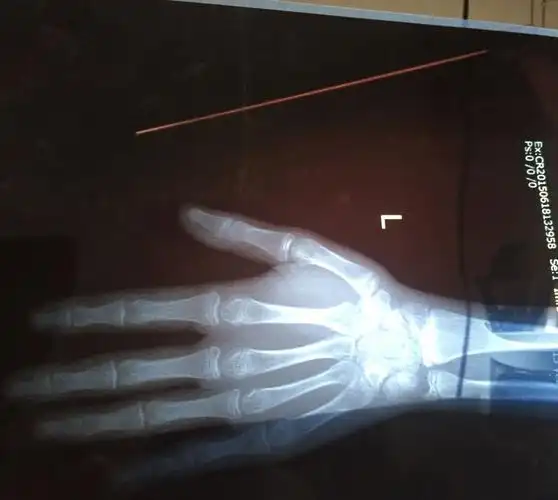

帮忙看下骨骺线闭合没,本人今年15岁,我还可以再长五公分吗

本人15岁,男,身高173厘米.照了双膝片,诊断得:双膝诸骨骺板已闭合.

今年15岁.男

我十五岁,看了三个医生,两个说还能长,一个说骨骺线闭合了,谁能看看

其三:小腿粗壮,身高几个月,一年内没有任何变化其二:骨骺线呈现闭合

难道就没希望了吗?男:20岁